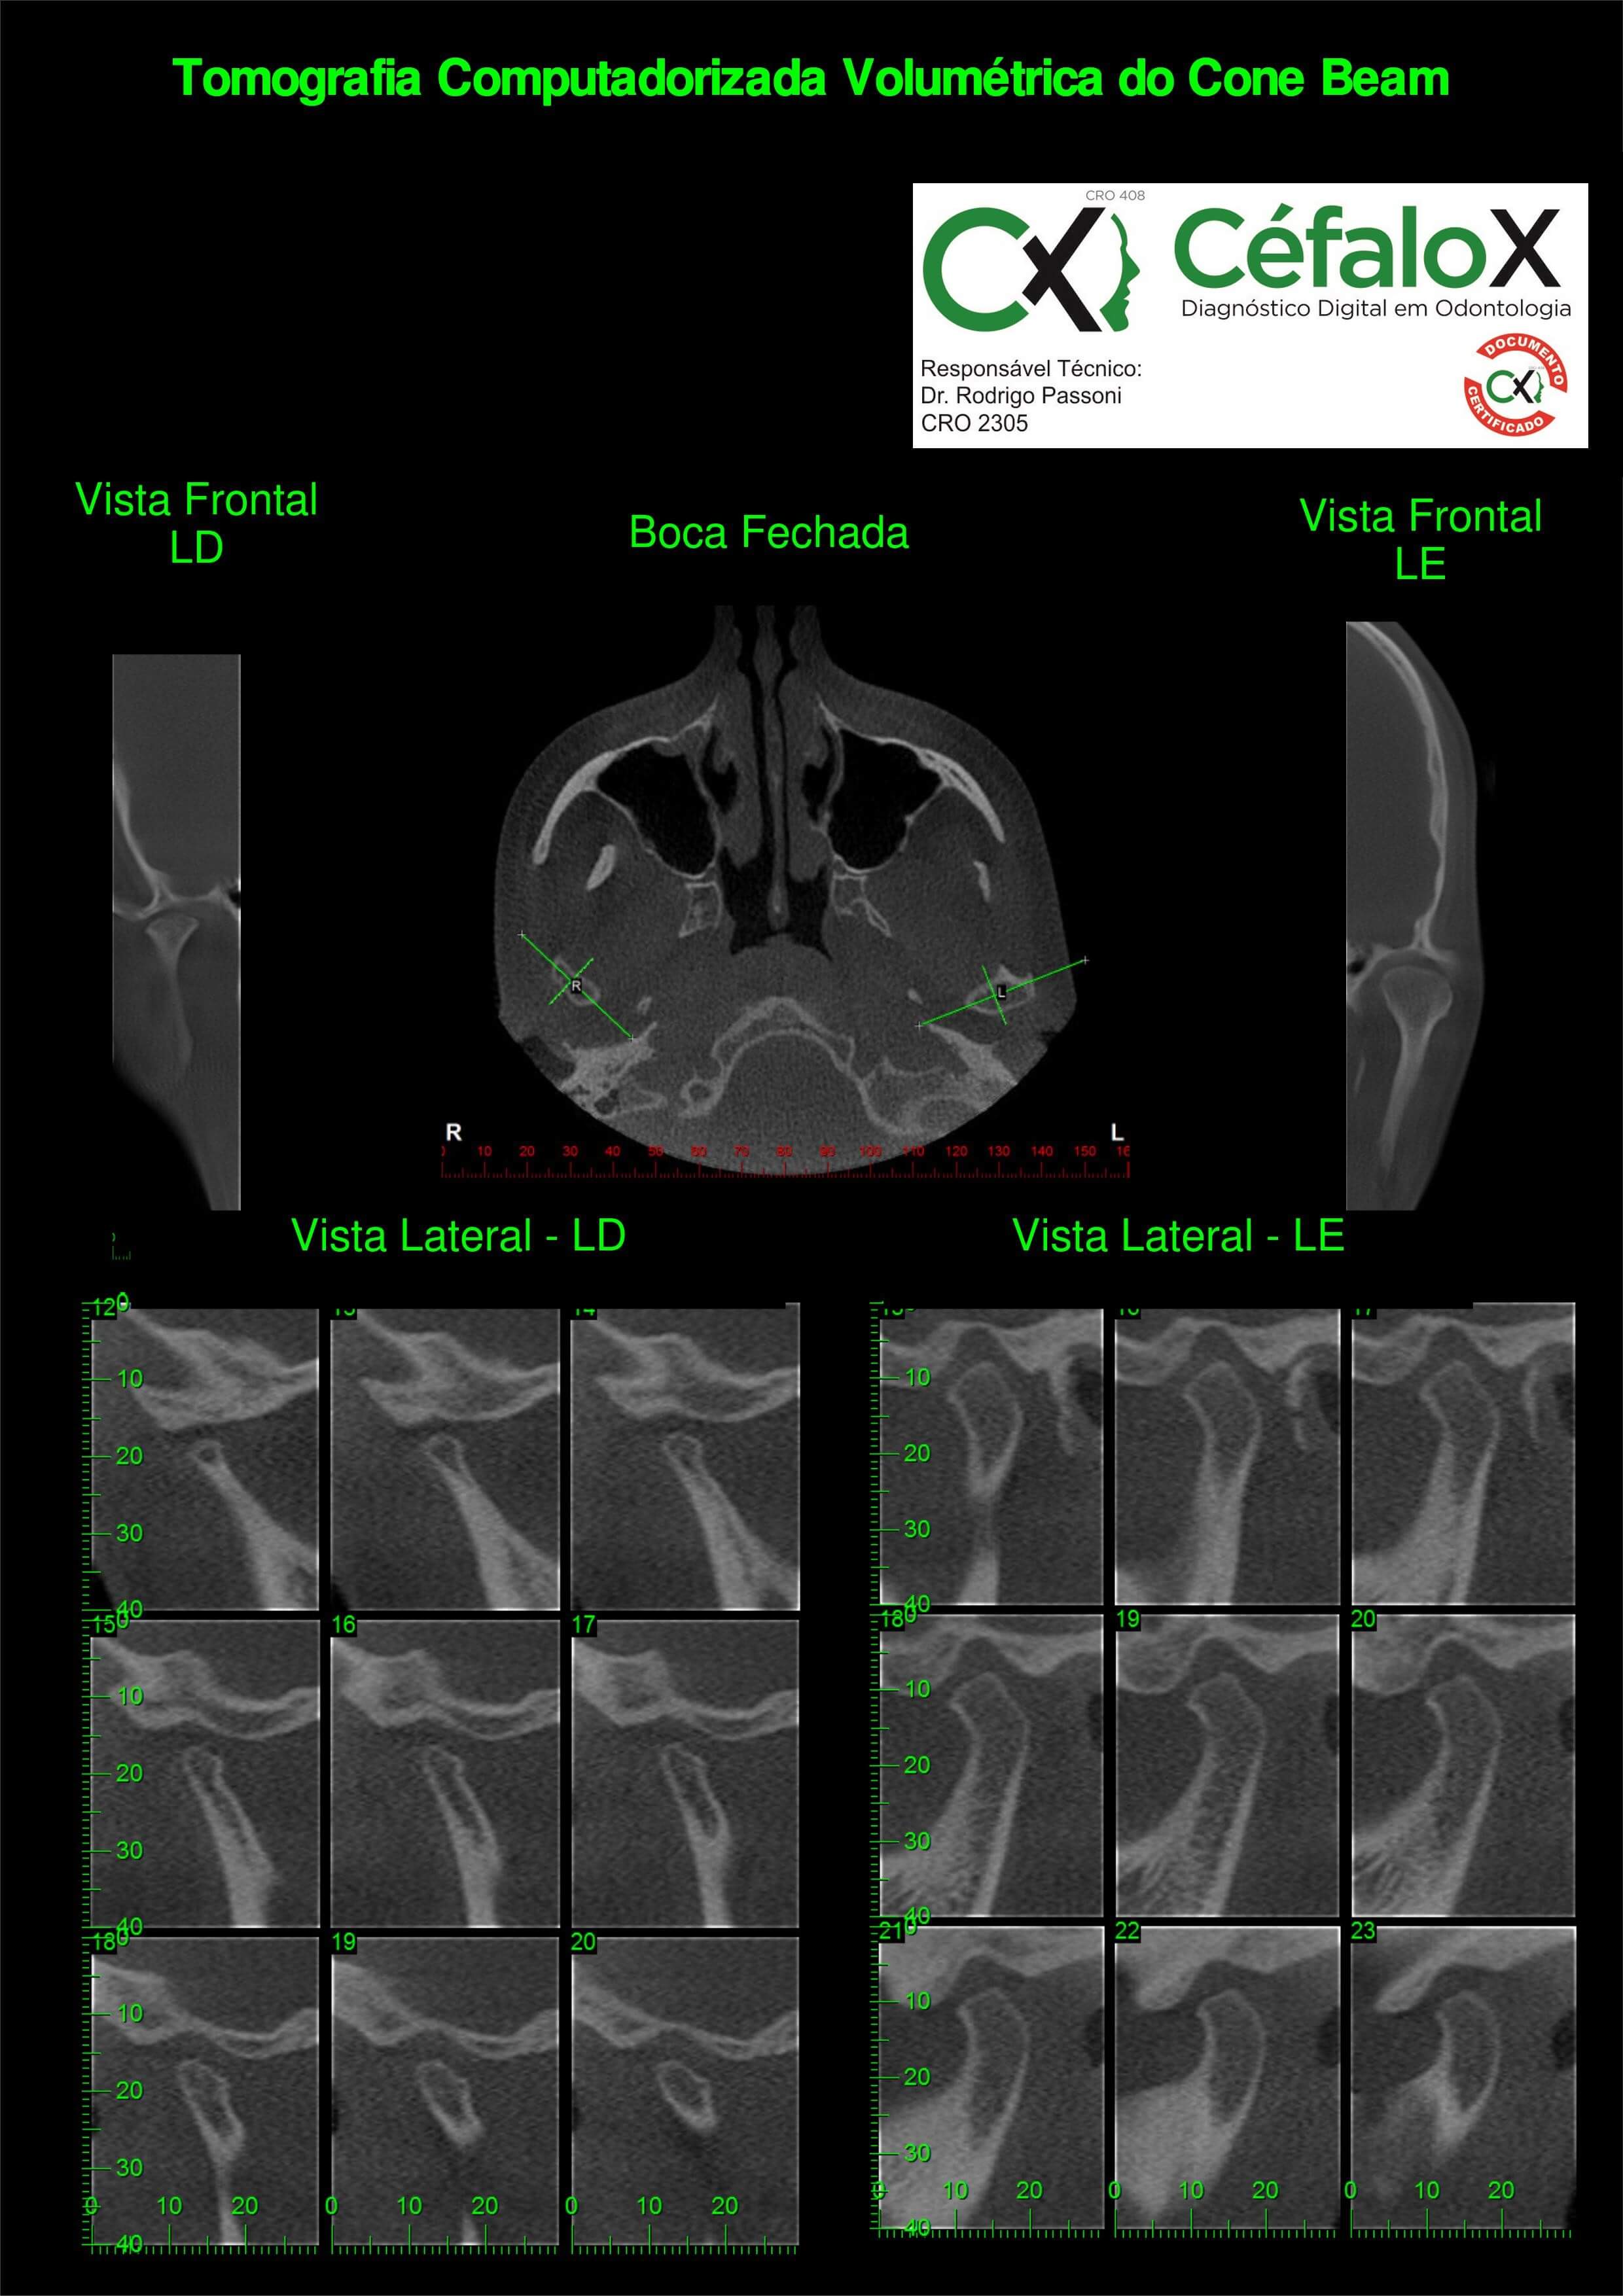

TC de face (do Hióide à Glabela), reconstruções 3D do tecido mole/ósseo/vias aéreas, radiografia panorâmica, telerradiografia lateral e frontal com traçado, cortes transversais e axial de maxila/mandíbula, ATM e arquivo DICOM – entregue em pasta e caixa de Pvc.